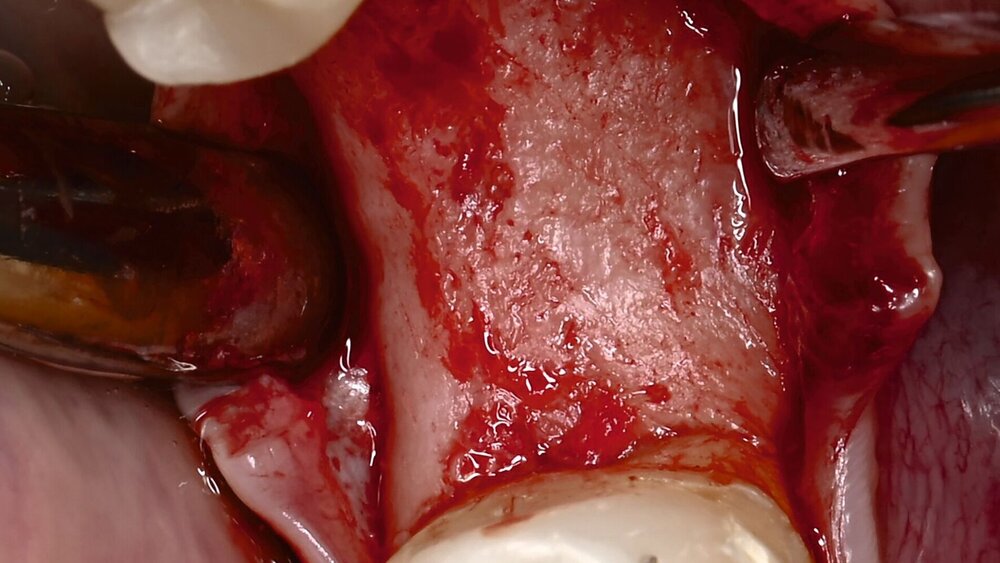

Als nächster Punkt wird der Zugang zum OP-Gebiet beurteilt. Liegt keine Einschränkung vor, befinden wir uns im S-Bereich. Die beiden nächsten Punkte betreffen Pathologien an den Nachbarzähnen und vorige Operationen im Implantationsgebiet. Die einfachste Situation ist, wenn weder Pathologien noch irgendwelche Voroperationen vorliegen. Bei der Beurteilung der chirurgischen Komplexität spielt die Ausheilung des Knochens eine Rolle, wobei die Implantation in eine ausgeheilte knöcherne Situation ohne Knochen-aufbauende Maßnahmen den einfachsten Fall darstellt.

Dann wird der Status der Weichgewebe erfasst und beurteilt: Bei einer Breite von mehr als 4 mm keratinisierter Mukosa ohne Narbengewebe und Entzündungen wird das Label S vergeben. Die Nähe von anatomischen Nachbarstrukturen ist der nächste Punkt, im S-Fall besteht nur ein minimales Risiko der Beteiligung. Das Vorhandensein der Papille an den Nachbarzähnen ohne Rezessionen stellt die ideale Situation dar. In der S-Variante befindet sich das Knochenniveau der Nachbarzähne auf der Höhe der Schmelz-Zement-Grenze, wobei ein gewisser Knochenabbau im Zusammenhang mit dem Verlust eines Zahnes einzurechnen ist.